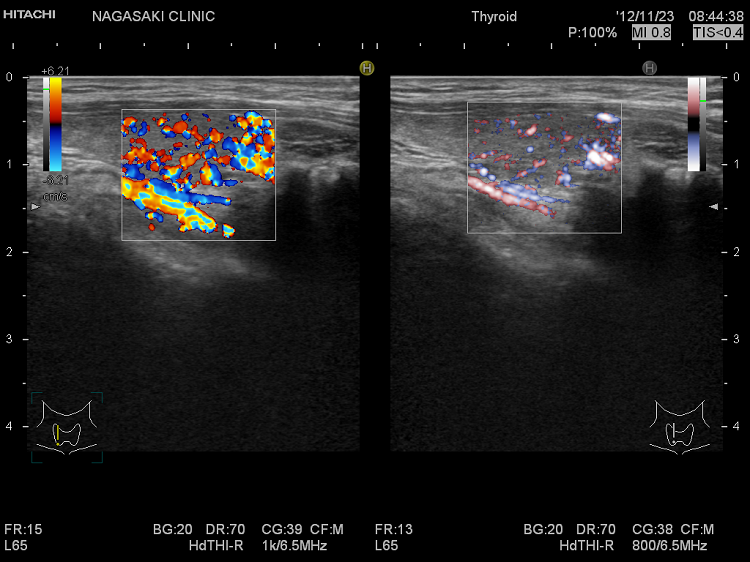

eFlow(イー フロー)と通常ドプラーの比較

(左)通常ドプラー;甲状腺内の血流のため、血管と周辺の甲状腺組織までが隠れてしまいます

(右) eFlow(イー フロー);甲状腺内の血管が鮮明に判ります

(左) eFlow(イー フロー);甲状腺内の血管が鮮明に判ります

(右) 通常ドプラー;甲状腺内の血流のため、血管と周辺の甲状腺組織までが隠れてしまいます